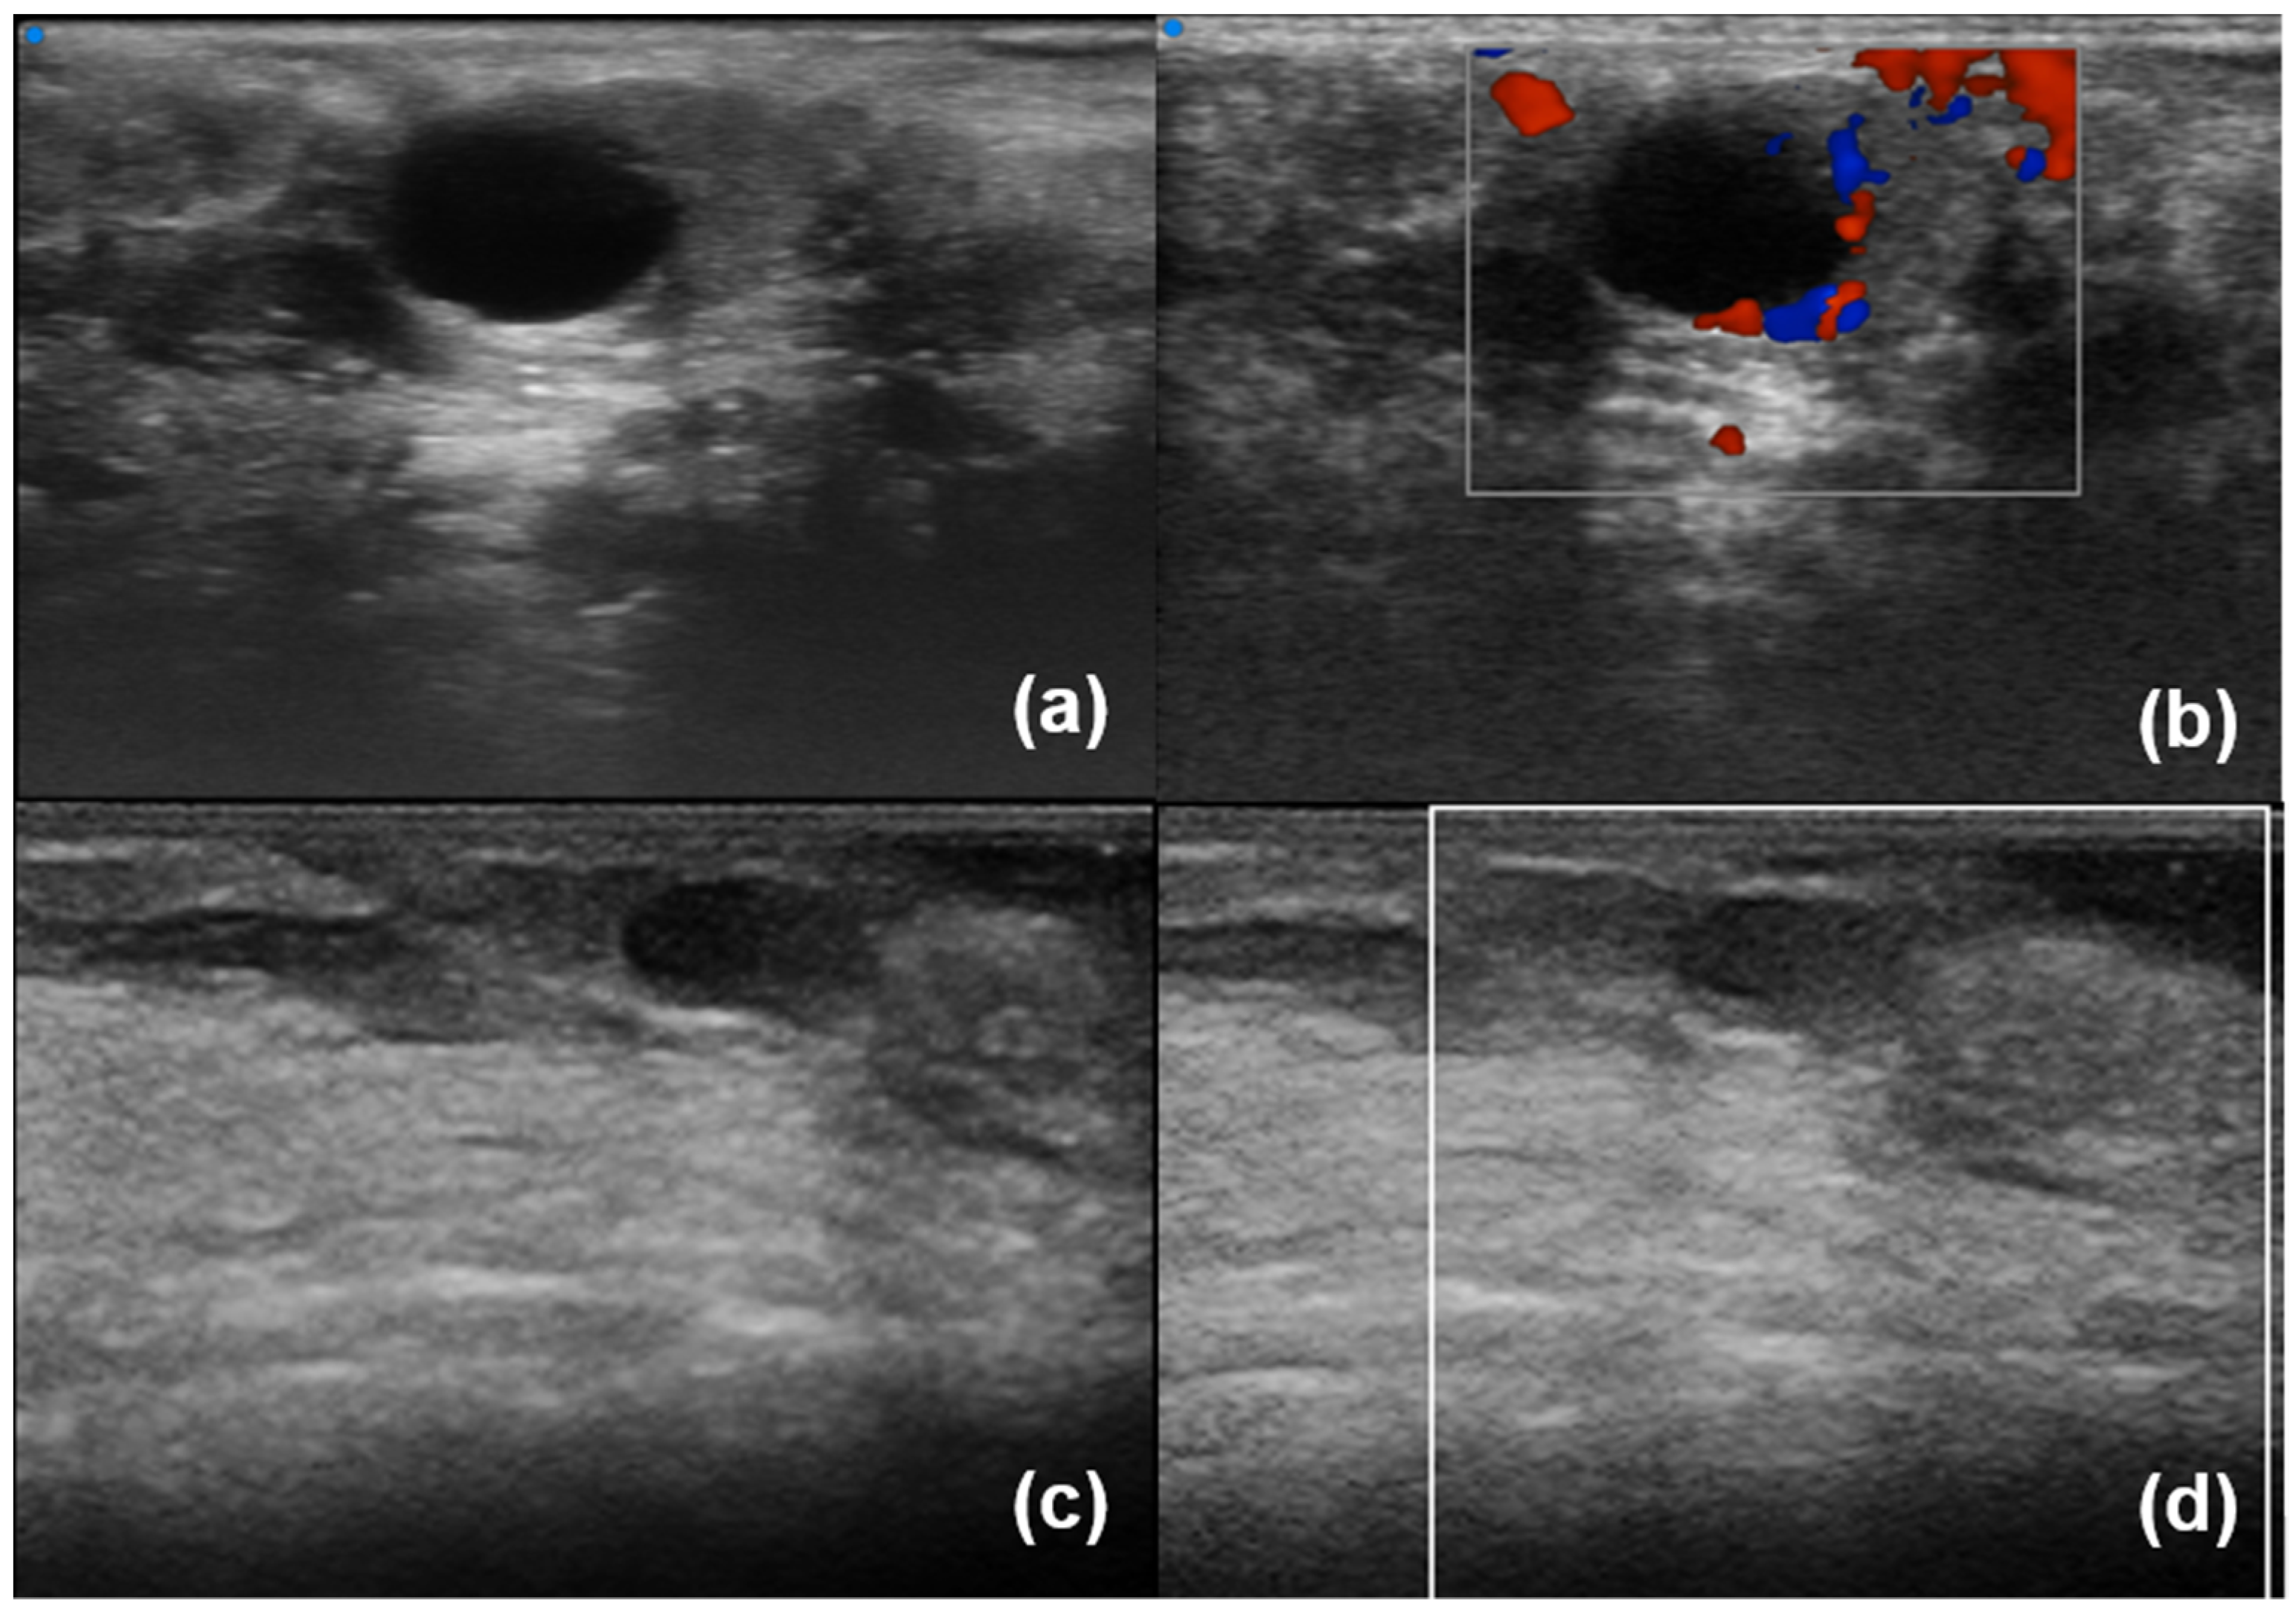

- Aringhieri, G.; Izzetti, R.; Vitali, S.; Ferro, F.; Gabriele, M.; Baldini, C.; Caramella, D. Ultra-high frequency ultrasound (UHFUS) applications in Sjogren syndrome: Narrative review and current concepts. Gland. Surg. 2020, 9, 2248–2259. [Google Scholar] [CrossRef] [PubMed]

- Fulvio, G.; Donati, V.; Izzetti, R.; Fonzetti, S.; La Rocca, G.; Ferro, F.; Baldini, C. Correspondence between minor salivary glands ultra-high frequency ultrasonography and histology: A case report of severe/atypical lymphoid infiltrate in Sjögren’s syndrome. Ann. Rheum. Dis. 2022, 40, 2474–2475. [Google Scholar] [CrossRef]